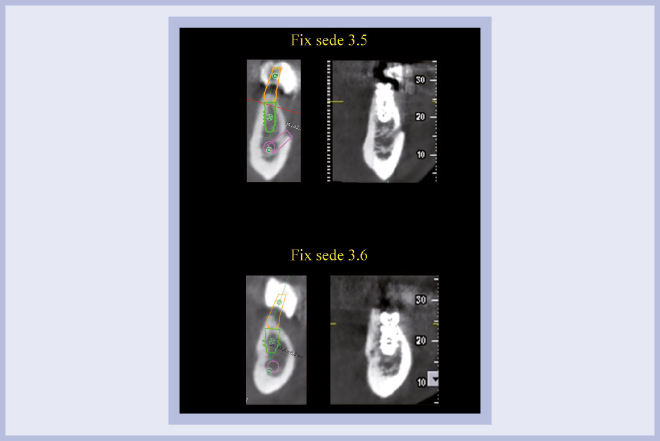

Per riabilitare la masticazione del terzo quadrante, con osso gravemente atrofico, si procede allo studio del caso con esame radiologico 3D e posizionamento virtuale di impianti Exacone® Leone. La prima valutazione è stata eseguita con il software dell’apparecchio radiografico Cone Beam presente in studio. Dopo aver verificato che la quantità di osso residuo fosse sufficiente all’inserimento di due impianti, seppur di dimensioni ridotte, in sede 3.5 e 3.6 senza l’ausilio di tecniche di rigenerazione ossea (Figg. 1-3), si richiede al laboratorio di confezionare una mascherina radiologica con ceratura diagnostica radiopaca e repere standardizzato a livello incisale come da protocollo Leone (Figg. 4, 5). Si verifica quindi clinicamente l’assenza di mobilità della mascherina dopo il posizionamento nel cavo orale del paziente (Figg. 6, 7). Si effettua una CBCT con la mascherina in posizione e l’esame viene inviato in formato DICOM all’azienda Leone assieme al modello master della paziente. L’azienda provvede quindi ad inviare agli Autori il software 3Diagnosys (software di progettazione) in licenza monopaziente con caricati i file DICOM ricevuti; il software viene quindi utilizzato per la progettazione definitiva del caso (Figg. 8-12).

- Figg. 8-12 – Pianificazione implantare con software 3Diagnosys Leone

- Fig. 9

- Fig. 10

- Fig. 11

- Fig. 12